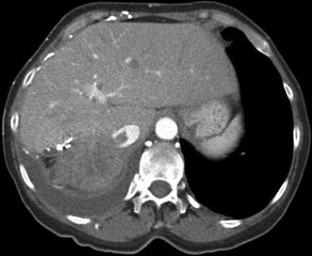

Treatment of Superior Vena Cava (SVC) Syndrome and Inferior Vena Cava (IVC) Thrombosis in a Patient with Colorectal Cancer: Combination of SVC Stenting and IVC Filter Placement to Palliate Symptoms and Pave the Way for Port Implantation

Thrombosis of the inferior vena cava is a life-threatening complication in cancer patients leading to pulmonary embolism. These patients can also be affected by superior vena cava syndrome causing dyspnea followed by trunk or extremity swelling. We report the case of a 61-year-old female suffering from an extended colorectal tumor who became affected by both of the mentioned complications. Due to thrombus formation within the right vena jugularis interna, thrombosis of the inferior vena cava, and superior vena cava syndrome, a combined interventional procedure via a left jugular access with stenting of the superior vena cava and filter placement into the inferior vena cava was performed As a consequence, relief of the patient’s symptoms, prevention of pulmonary embolism, and paving of the way for further venous chemotherapy were achieved.

Fig. 2